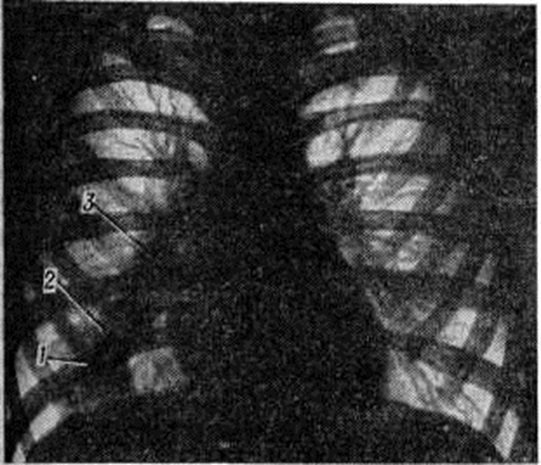

Рис. 1.

Гистотопограмма лёгкого при первичном туберкулёзном комплексе: 1 — очаг казеозного некроза в лёгочной ткани в стадии начавшегося отграничения; 2 — казеозный некроз лимфатических узлов в области корня лёгкого; 3 — воспалительные изменения лимфатических сосудов, соединяющих очаг в лёгком с лимфатическими узлами корня лёгкого — туберкулёзный лимфангиит.